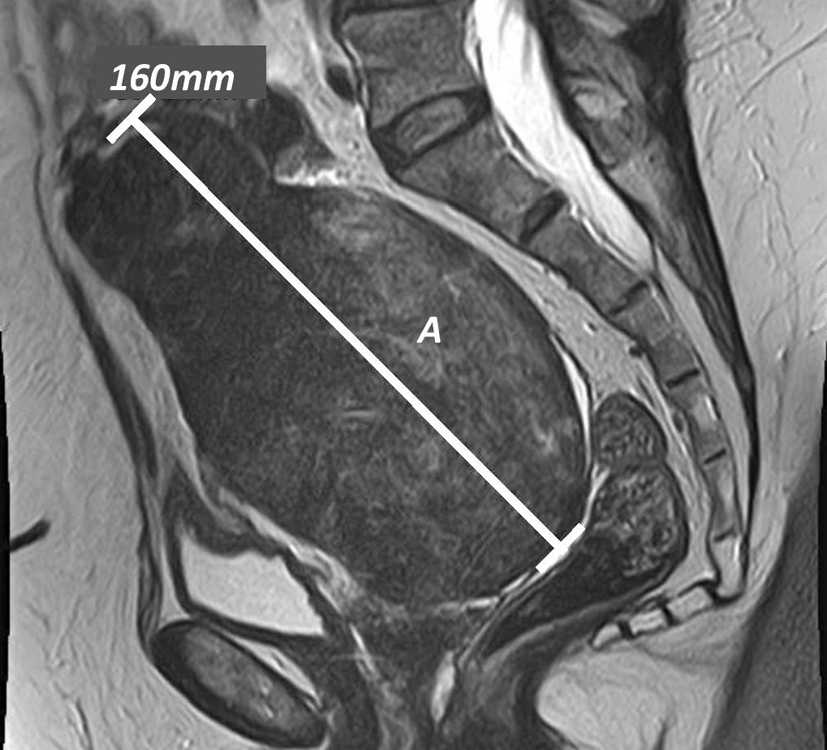

A 73-year-old female patient presented in clinic with a 1-year history of irregular bowel habit but no weight loss, abdominal pain or significant medical or surgical history. Esophagogastroduodenoscopy and colonoscopy carried out 1 year prior showed she had a hiatus hernia, duodenitis and diverticular disease. Abdominal ultrasound performed 4 years earlier showed the presence of cholecystolithiasis. A computerized tomography of the chest, abdomen and pelvis (CT-CAP) was performed and showed evidence of gallbladder perforation with a 3 cm stone at the neck of the gallbladder and a 4 × 3 cm intrahepatic abscess but no evidence of biliary dilation (Fig. 1); an incidental large cystic pelvic mass was also seen. Magnetic resonance imaging (MRI) of the pelvis revealed a large low signal pericystic mass posterior to the uterus measuring 16 × 10.7 × 14.6 cm suggestive of a pedunculated leiomyoma (Fig. 2). A drain for the liver abscess was placed whilst multi-disciplinary team (MDT) discussion on further management was awaited.

![]() Click for large image | Figure 2. Sagittal T2 pelvic MRI: (A) pelvic mass. |